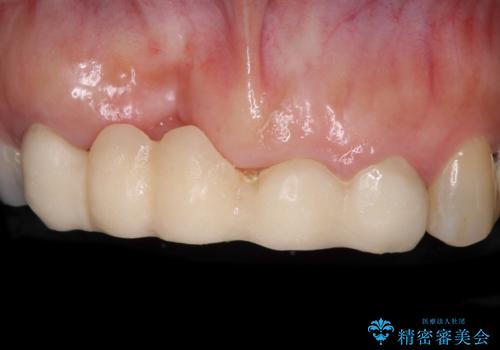

手前の歯はむし歯の範囲が広いためオールセラミッククラウンにて、最後方歯は部分的なむし歯であったのでPGAインレー(プラチナゴールドインレー)にて治療を進めることとしました。

仮詰めの状態が良くなかっただけで、むし歯が神経組織にまで及んでいることはなく、無事に治療を終えることができました。